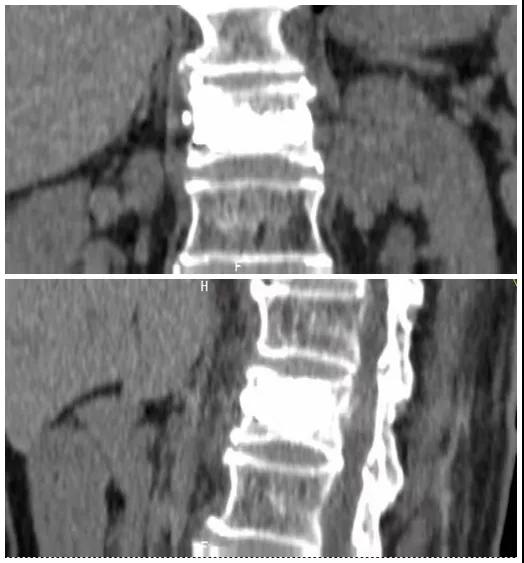

術(shù)后復(fù)查CT可見(jiàn)骨水泥彌散充分